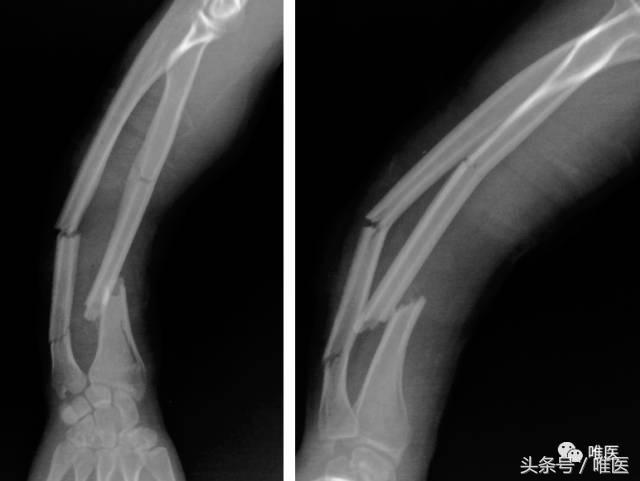

▣ 女性,21岁,右前臂多段双骨折。

▣ 术后正侧位片